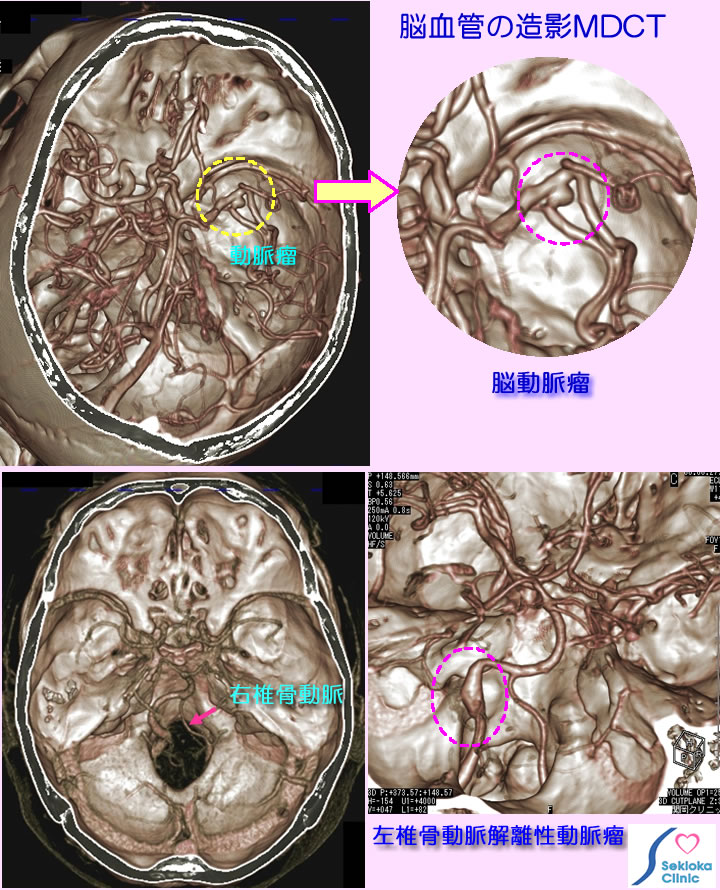

| 他の検査法との関係 | 頸動脈超音波エコー、脳血管MRA検査などの後に精査でMDCTよる血管造影検査(MDCTの方がMRAより空間分解能が高い、一方造影剤が必要)が行われる場合もありまます。添付画像上段は脳動脈瘤(破線円内)の例です。下段右は、後頭・頸部の痛みで受診、造影MDCTで椎骨解離性動脈瘤を認めます。動脈瘤が破裂するとくも膜下出血となり激しい頭痛・意識障害を生じる危険な病気です。下段左は他院のMRA検査で右椎骨動脈の閉塞と言われ来院され、MDCTで検査した例です。MDCTでは閉塞ではなく血管が左に比べ細いことがわかります、椎骨動脈では左右血管径の非対称は時々認められます。 |